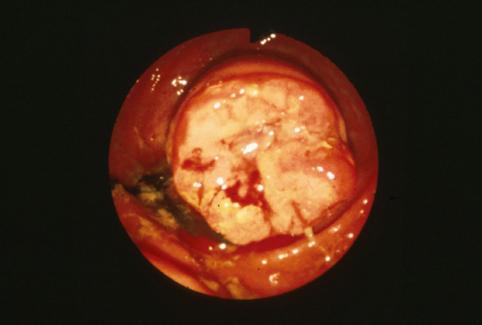

疾患(病理主体)の分類悪性上皮性腫瘍/腺癌

部位(臓器別)大腸/虫垂

検査方法内視鏡

腫瘍の肉眼分類2型(潰瘍限局型)/

病変の最大径(ミリ)25〜29

腫瘍の深達度s(a)